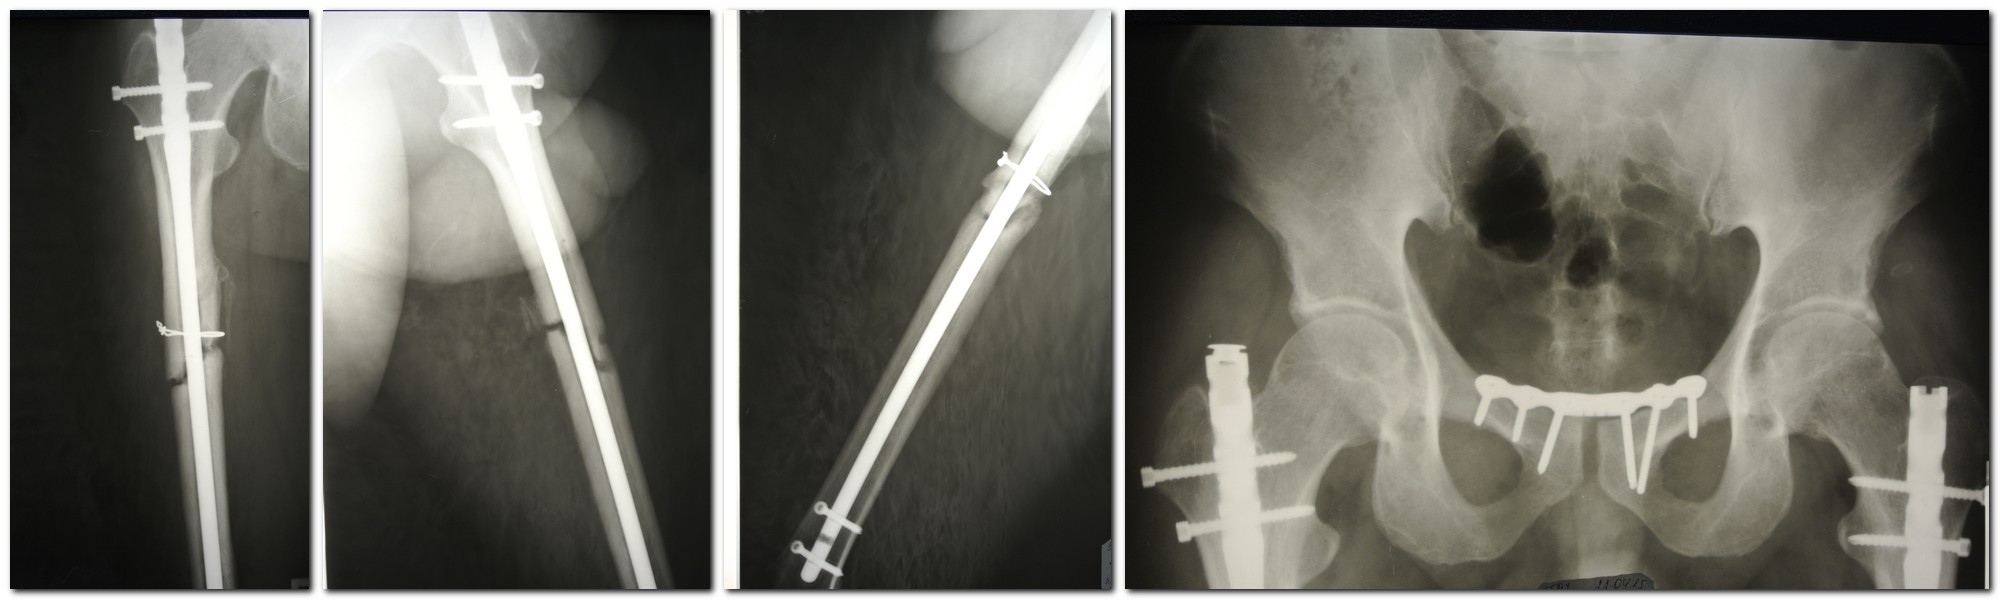

Уважаемые коллеги, помогите пожалуйста с производителем стержня. Пациент 34 года, оперирован год назад в Турции по поводу множественной травмы: наложение АВФ на таз по поводу разрыва симфиза и БИОС обоих бедер, судя по ранам после перевода к нам в стационар - остеосинтез был открытый. Нами выполнен металлодез лонного сочленения. Пациент активизирован, выписан в удовлетворительном состоянии. Динамизация не проводилась. В настоящее время клиника а также Р-кая картина ложных суставов обоих бедер. Тактика понятна, непонятно только как удалять стержни, производитель неизвестен. По данным меддокументации и ответа на запрос в турецкую клинику данных о фирме производителе стержня тоже информации нет. Спасибо.

Какая клиника псевдоартрозов? По виду похож на Турецкий ChM.

Если нет ротационного смещения, то может дать полную нагрузку и понаблюдать 3 мес.... Еще вводят лидазу с анестетиком (маркаин) в область псевдоартроза - есть хорошие результаты, данный случай - подходит.

Запросто может оказаться что-то местное, их там много разных. Надо поискать универсальный экстрактор конической формы - если все-таки придется удалять, но время есть.

Вот и начать бы с нее пока. И появится несколько месяцев на подготовку инструментов.